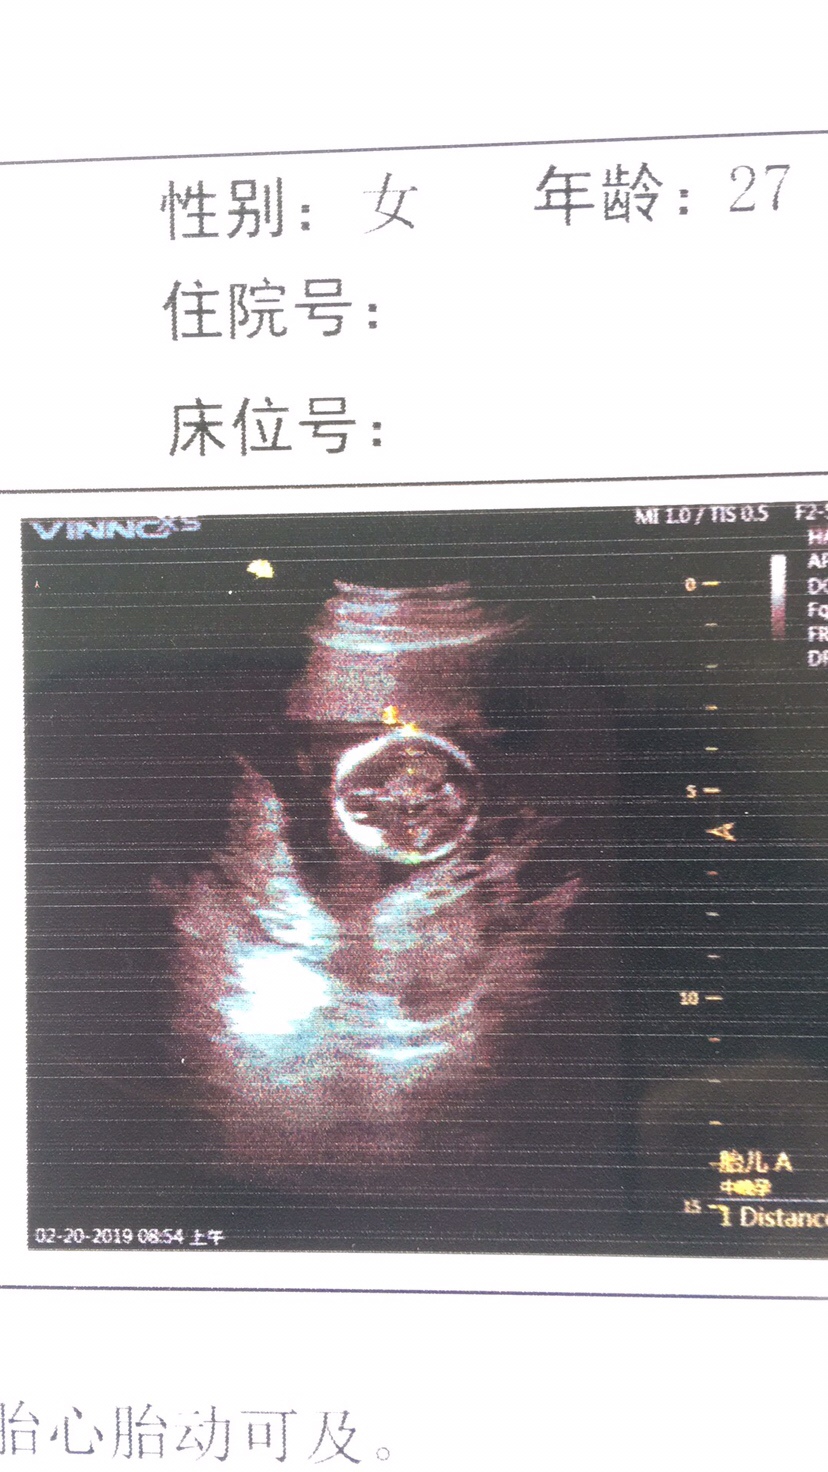

可乐双胞胎兄弟

2018-06-01

2736 人回复